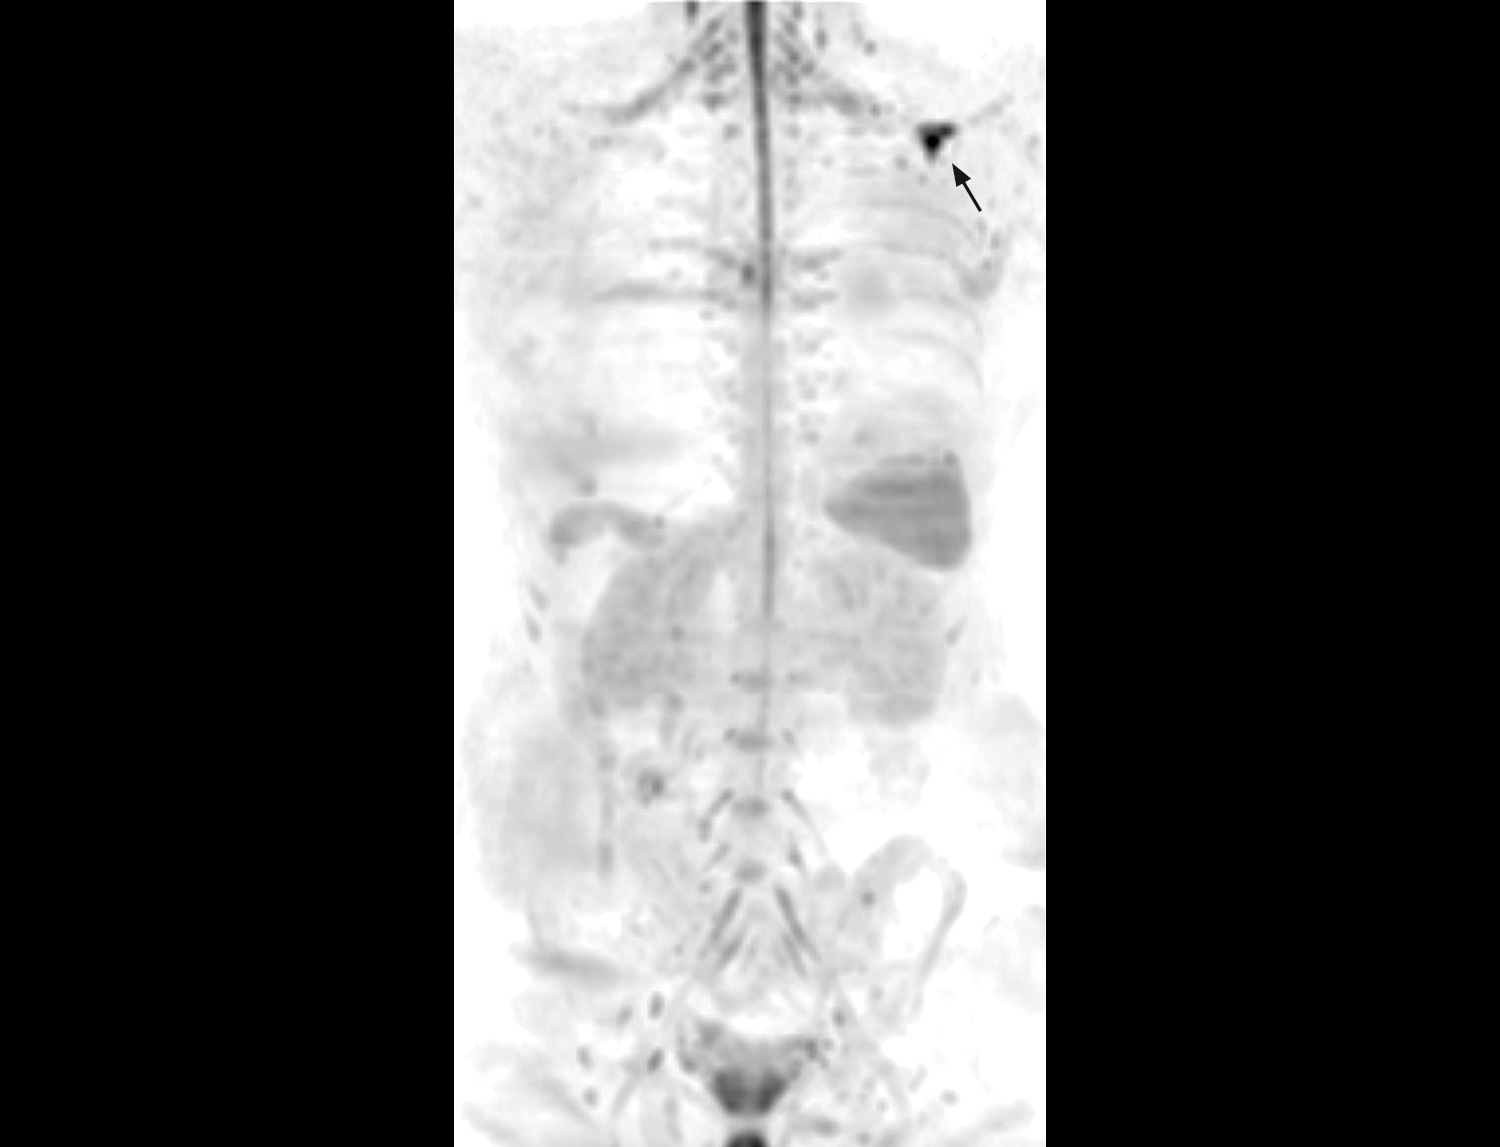

A 33-year-old male with history of non-Hodgkin lymphoma undergoes an MRI exam on Ingenia 1.5T to visualize clinically suspected recurrent disease. Whole-Body MRI was performed using T1W TSE and STIR imaging (4 stations, matrix 400x400, 6 mm slices). Additional whole-body diffusion imaging (3 stations, matrix 192x192, 6 mm slices) with MIP unmasks a focal area of diffusion restriction in the left scapular region. Subsequent contrast-enhanced 3D mDIXON imaging reveals a bone manifestation of a lesion in the left scapular angle. Furthermore, multifocal splenic infiltration is depicted. Note that the splenic lesions are veiled by the high physiological background diffusion signal in splenic tissue. The findings are compatible with skeletal and splenic tumor recurrence of non-Hodgkin lymphoma. Further total body follow-up imaging according to therapeutic regime is advised. Whole-body MRI allows rapid visualization of lesions in this lymphoma patient. A finding of multifocal organ manifestations has a decisive impact on further patient management and therapeutic regime. The fully digital Ingenia 1.5T MR system allows for rapid whole-body MRI with homogenously high imaging quality in depicting these lesions. Additionally, state-of-the art techniques such as whole body DWI can be included in the exam protocol, which further enhances the capability for visualizing lesions in oncology patients.

DWIBS